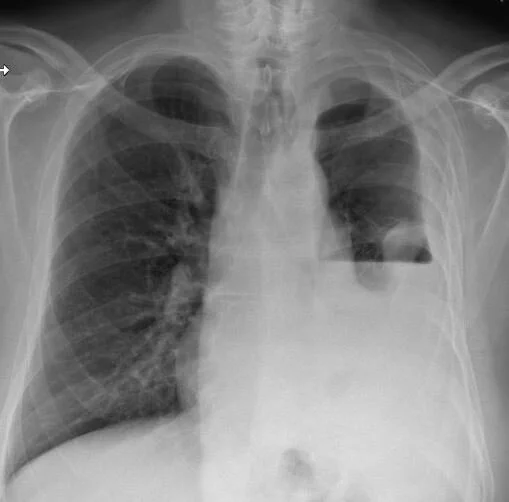

A 61 y.o. homeless man complains of fever and cough

his cxr is shown below

What does it show?

Our patient had an empyema growing out strep mitis and MSSA. .Empyema describes gross pus in the pleural cavity.  It was first described by Aristotle in 300 BC when he placed a metal tube into a patients chest. If it persists for several weeks fibrin deposits on the visceral and parietal pleura leading to entrapment of the lung. An air fluid level forms if there is a gas forming organism like an anaerobe or a bronchopleural fistula. The air fluid level forms a distinctive straight line on the cxr.

In our patient, ten days after his second hospitalization his air fluid level continued to increase on antibiotics with the chest tube draining.  He was scheduled for a decortication by thoracic surgery.